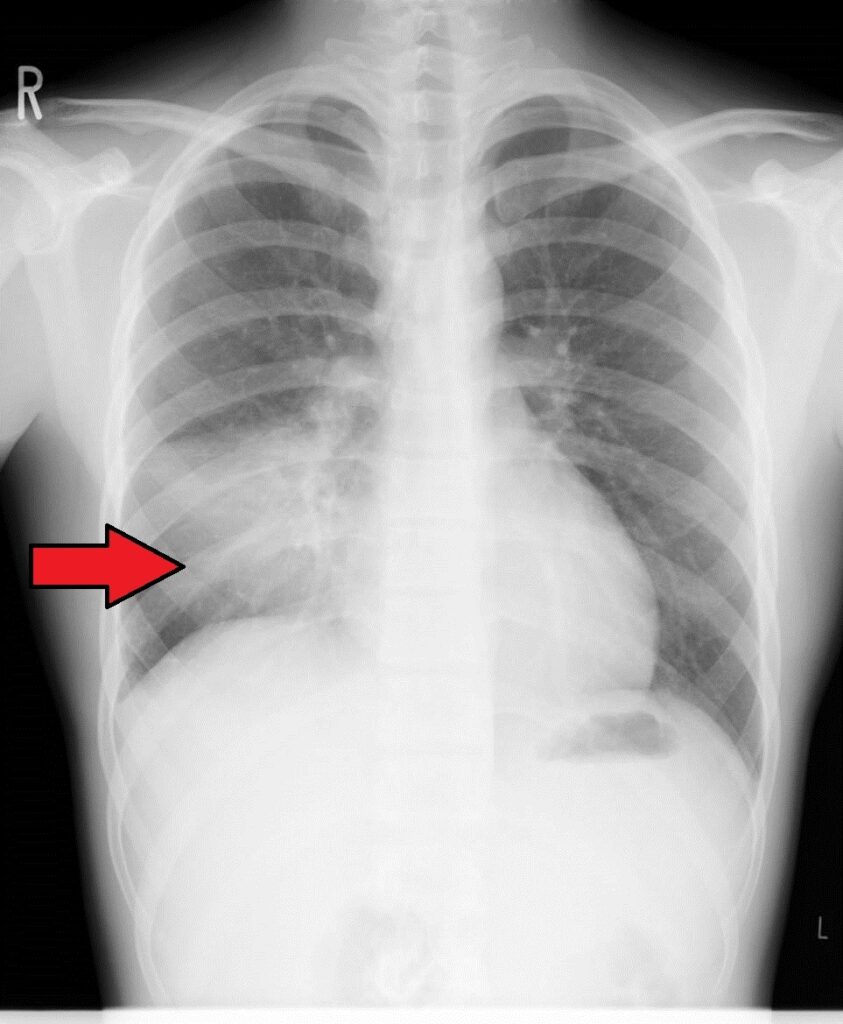

気管支炎、肺炎

病原体が気管支や肺でわるさをし、炎症を起こしてしまう状態です。細菌やウイルスなどが原因となり、細菌が原因の場合には抗菌薬を使用します(ウイルスが原因の時には抗菌薬は無効です)。また症状を和らげるためにいくつかの薬を併せて使用することもあります。